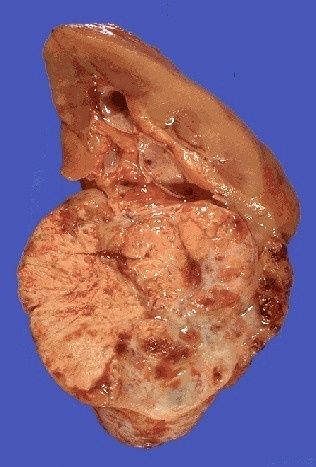

| Tumor de Wilms |

Image:

Renal058 (image/jpeg)